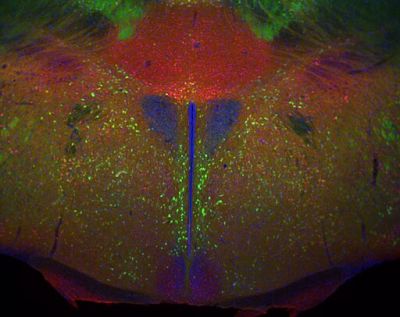

Hypothalamus, mouse – histology slide

The hypothalamus from a D2-eGFP (green) transgenic mouse stained for calretinin (red) and DAPI to show nuclei.